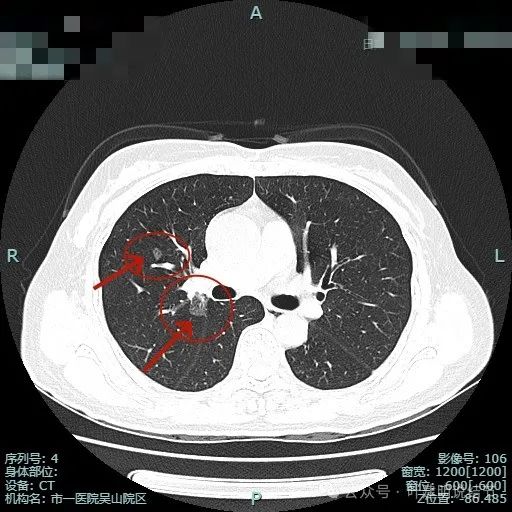

右上主病灶出现(病灶2),离肺门部非常近,密度较淡。

病灶1有明显叶间裂牵拉影响;病灶2密度虽淡,但轮廓清,贴着支气管壁。也有小血管走向病灶。

病灶1密度已经淡了;病灶2刚好位于上叶支气管发现后段支气管处,与支气管壁没显著间隙。

病灶1已经淡,且靠降主动脉近;病灶2密度其实也不纯,灶内有微小血管穿行,边缘侧有血管贴边,与支气管管壁间没有间隙。

1、患者多发磨玻璃结节,均考虑是肿瘤范畴的。相对来说病灶2最大,病灶1收缩力最明显,而且密度相对更不纯。病灶3与病灶2类似密度,病灶4过小没有意义。

2、病灶2贴着斜裂,表面不平,考虑至少是微浸润性腺癌,也可能是浸润性的,而它贴着叶裂,不处理存在一定风险。病灶1也密度不纯,同样有风险,需要干预。但从位置形态以及病灶个数来讲,右上的宜优先处理。因左下的到时候只需简单小范围的楔形切除便可。当然也不能随访过久,待右侧手术后恢复相对较为正常,就可考虑也予以手术了的。